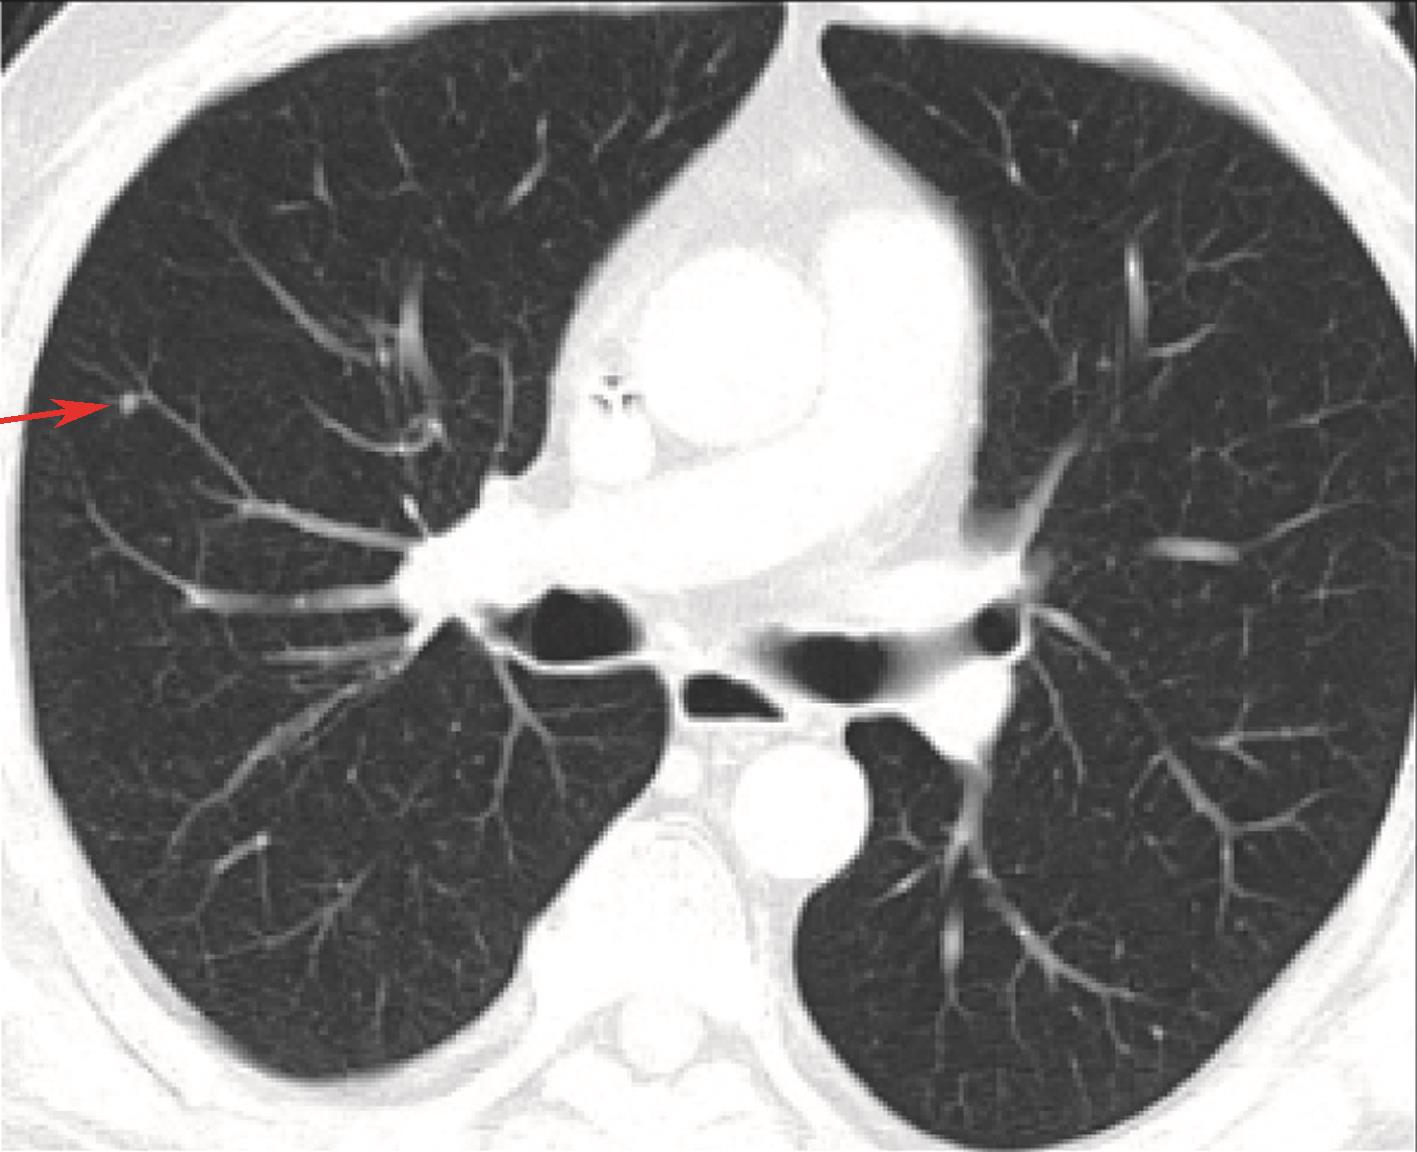

1小时条评论55岁女性,因左下腹反复疼痛2月余,加重1个月就诊,腹部CT可见肾脏及盆腔两处新生物,如何诊治? 【病例摘要】 患者,女性,55岁,因左下腹反复疼痛2月余,加重1个月就诊于四川大学华西医院。查体:下腹部触及8cmtimes;7cm包块,质韧,活动性差。 既往史及家族...